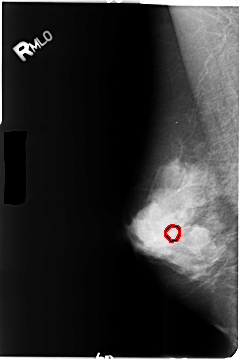

FILE: B_3480_1.RIGHT_MLO.OVERLAY

TOTAL_ABNORMALITIES 1

ABNORMALITY 1

LESION_TYPE CALCIFICATION TYPE PLEOMORPHIC DISTRIBUTION CLUSTERED

ASSESSMENT 4

SUBTLETY 3

PATHOLOGY BENIGN

TOTAL_OUTLINES 1

BOUNDARY